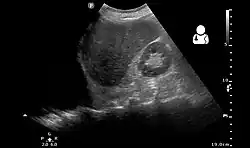

Ultrasonography may be used to detect hemothorax and other pleural effusions. This technique is of particular use in the critical care and trauma settings as it provides rapid, reliable results at the bedside.[23] Ultrasound is more sensitive than chest x-ray in detecting hemothorax.[25] Ultrasound can cause issues in people who are morbidly obese or have subcutaneous emphysema. When CT is unavailable in the current setting or the person cannot be moved to the scan, ultrasound is used.[3]

Ultrasound scan of the chest showing a left-sided hemothorax -

Ultrasound can detect blood in the pleural cavity. Blood in the thorax is shown by a uniform area without flocculation.[40] Pleural effusions without blood are usually hypoechoic. Echogenicity is indicated by cellular debris and/or fibrin. Bloody pleural effusions are shows by a swirling, hyperechoic pattern.[38] When a stethoscope is used (auscultation), the heartbeat sounds are faint. When percussion is performed, it produces a dull area. However, especially in traumatic cases, percussion may be painful. Although nonspecific, physical examinations may show reduced lung sounds and muffled, widespread heart sounds. Similar signs and symptoms may occur when other fluids are in the pleural cavity.[40]